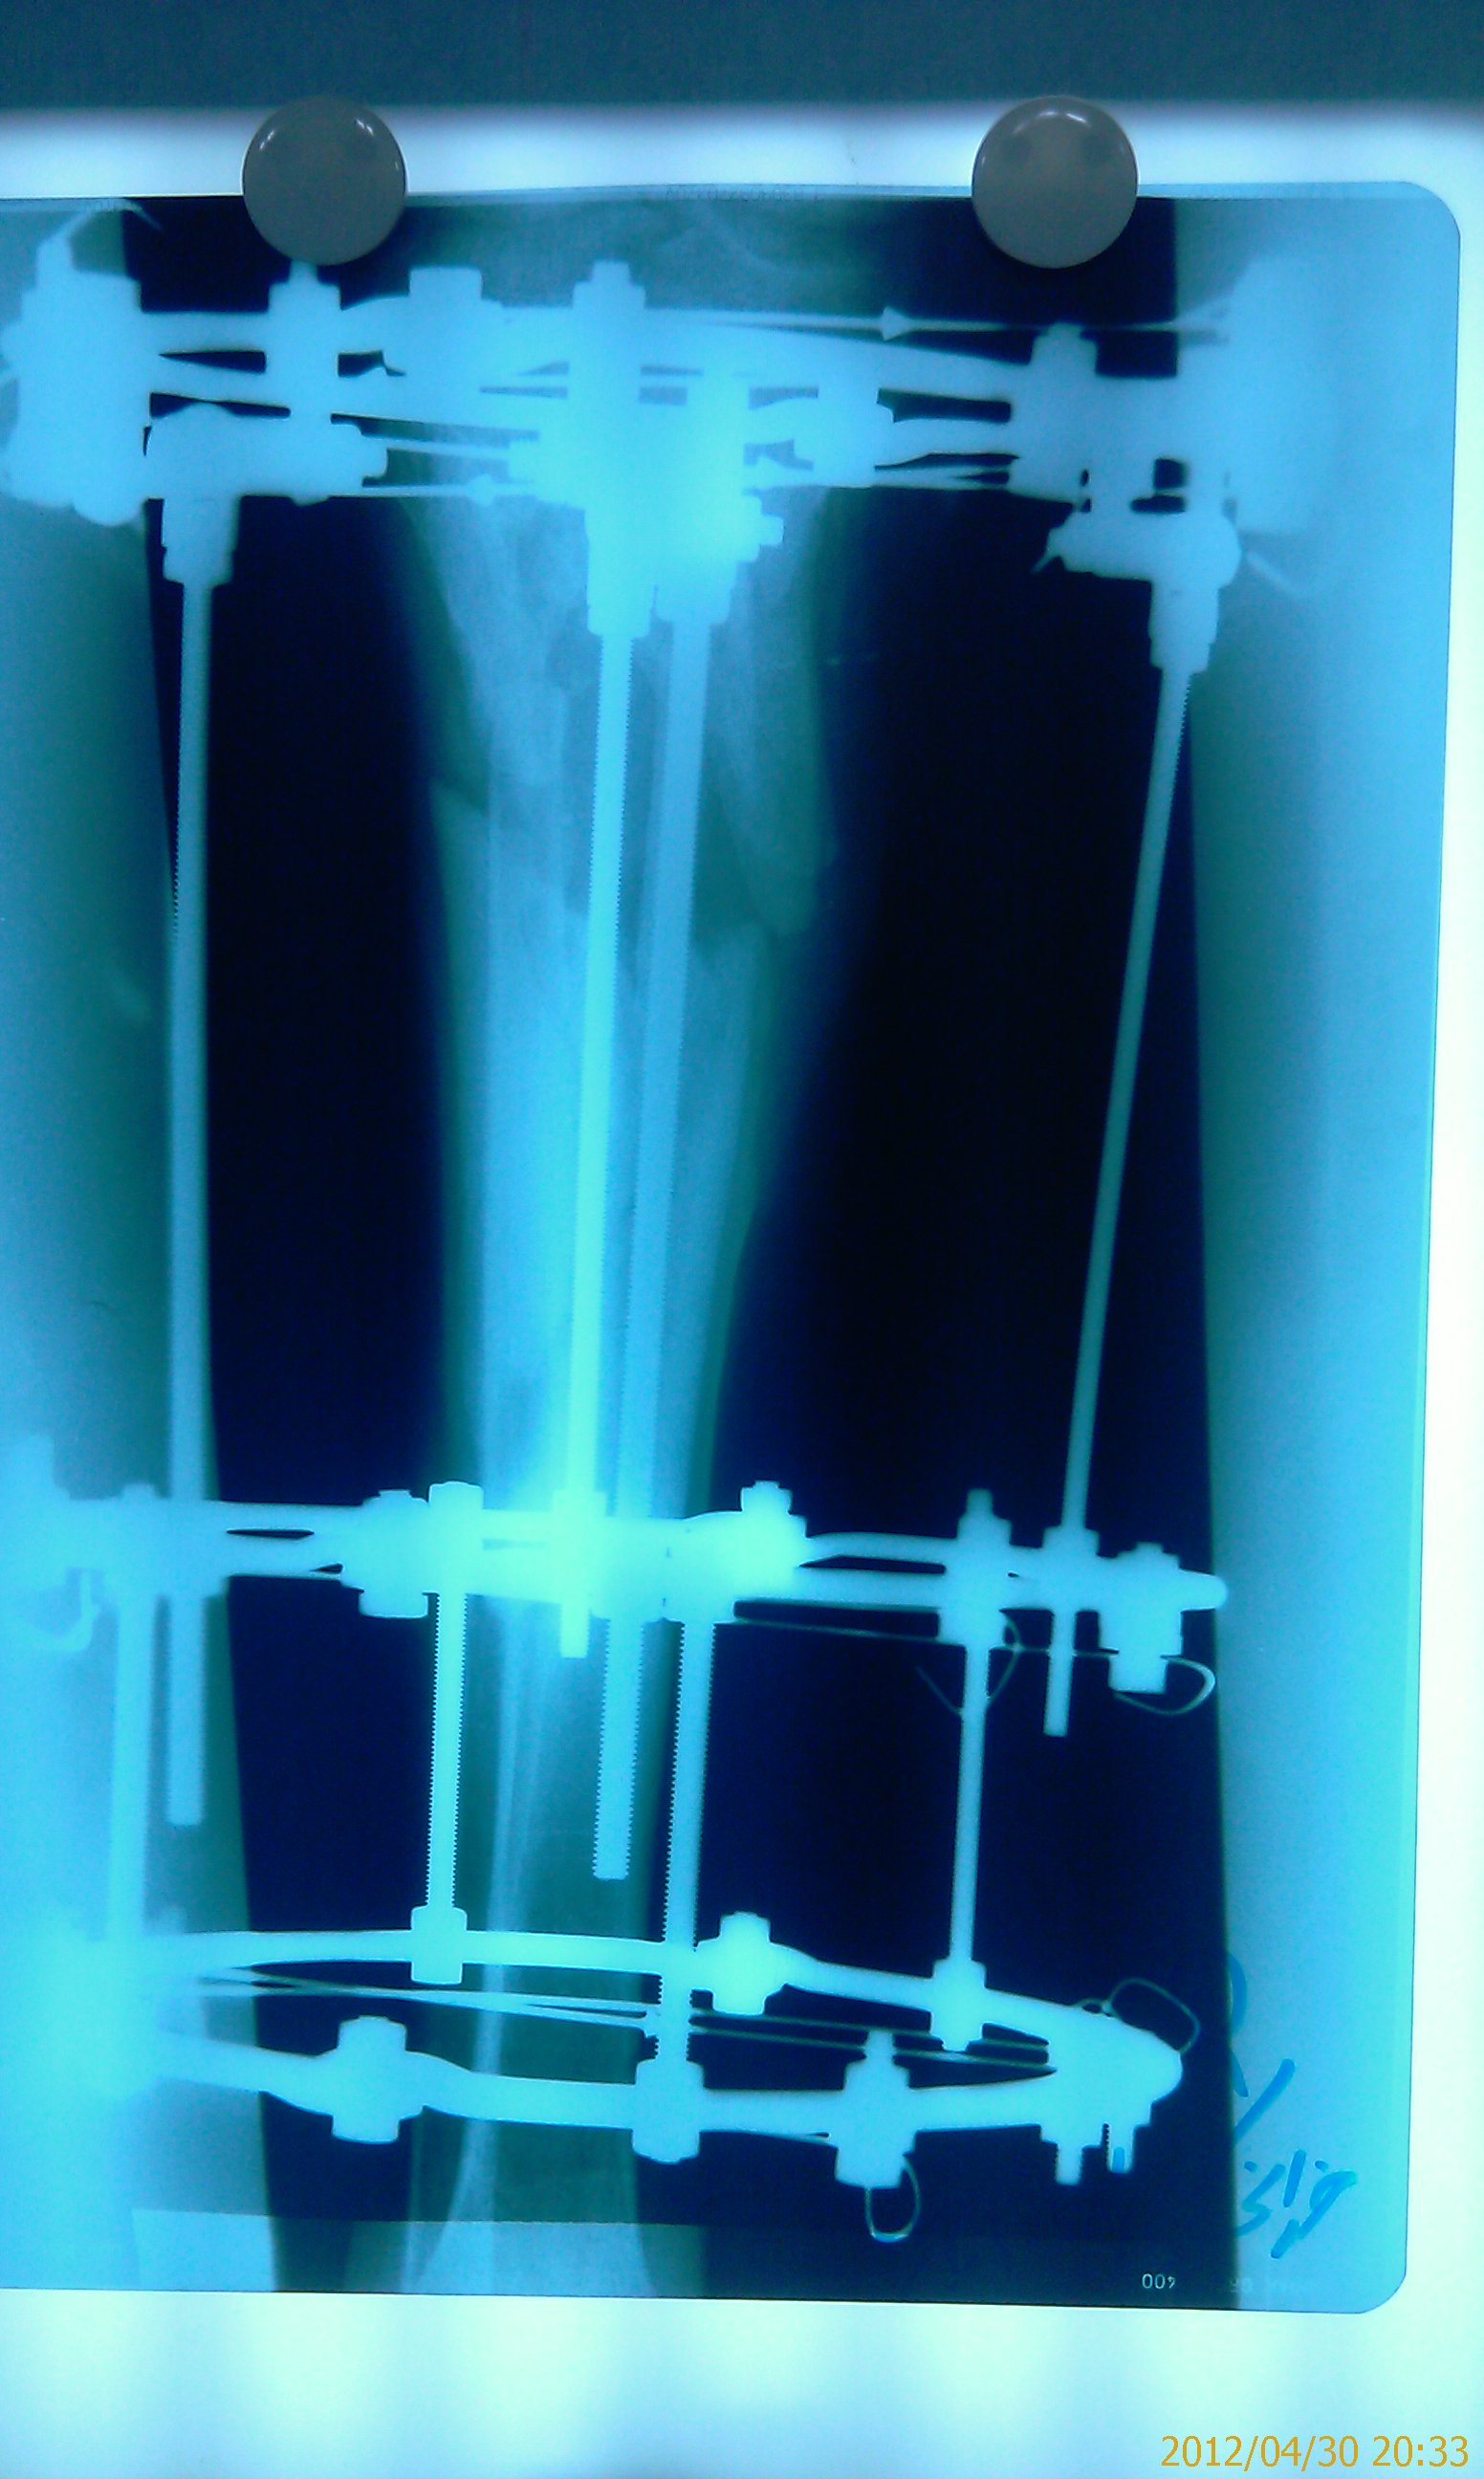

تهیه و تامین تجهیزات ارتوپدی و مشارکت در انجام اعمال جراحی ارتوپدی و عمل‌های نادر عضو تیم جراحی افزایش قد -جهت ترمیم شکستگی های قدیمی و جوش نخورده گی ها -طویل کردن اندامها- طویل کردن انگشت قطع شده - تعویض مفصل لگن _تعویض مفصل زانو _ بازسازی رباطACLوPCL_اصلاح ناهنجاریهای مادر زادی -با همکاری پزشکان و متخصصان مجرب آموزش دیده در روسیه و اتریش و سوئیس بروش جراحی ایلیزاروف و lon و lsa و واگنر و اسلایدینگ نیز جدید ترین روش افزایش قد و اندام در سال 1397 بنام hil هیل برای اولین بار- افزایش قد به 6 روش جراحی و جدیدترین روش در اروپا و روسیه. آدرس مطب _تهرانسر بلوار اصلی مجتمع سهند طبقه4 واحد 410

قطعات الیزاروف:

الیزاروف دارای عناصر اولیه و عناصر ثانویه است:

Bolt slotted-pin-ringعناصر اولی:

ها را به هم وصل می کند. .ringعناصر ثانویه: تمام قطعاتی که

پین ها باید در دو طرف رینگ گذاشته شود تا رینگ تاب نخورد،واشر کونیکال یا اسفریکال واشر تا 5/7(نیست به رینگ) درجه زاویه به راد می دهد .

باکل:وسیله ای که روی رینگ می چرخد                                            رینگ اومگا:برای بالای بازو و (یاهومروس)

rodیاpostفراموش نشود: استفاده از واشر شیار دار زیر

برای فیکس یک قطعهrodفراموش نشود  استفاده ا ز  واشر شیار  دارد در وسط

وایر ا لیزاروف  باسر بایونت(سوراخ کردن دیافیز) و تروکار(سوراخ کردن متافیز داپی فیز- سر پهن دارد)

-مقدار کشش وایر بین 130تا50 کیلوگرم است .

-  اگر نتوان دهانه تنشنر را روی رینگ گذاشت باید بین آنها یک سوکت قرار داد .

- مکعب رزوه دار برای نصب پین در زاویه های مختلف هم مفید است .

-در زاویه های مختلف هم مفید است .shan2مکعب رزوه دار برای نصب -

نیز مفید است که می توان روی مکعب روزه دار نیز وصل شود .drop wire- استفاده از هالف پین به جای

درهرکدام کافیست حلقه drop off- بلند کردن تی بیا بیش از 5تا6:دو حلقه با دو وایر در هر کدام و یک وایر

پایین موازی محور آنکل حلقه بالا برای مقابله با فشار عضلات پوستر ولاترال در7والگوس و10درجه فلکشن نسبت به ساق و

حلقه پایین و مصل زانو است.یعنی دو حلقه در قسمت جلو ازهم باز تر و در قسمت مدیال نیز ازهم باز تر هستند .